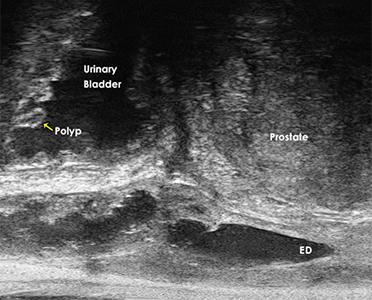

The 29 MHz ExactVuTM system facilities resolution down to 100 microns – and enables

detailed visualization in real-time of the prostate anatomy and characterization of

the prostatic tissue.

The following are select cases that are routinely derived from the ExactVuTM

micro-ultrasound platform and verified with pathological results.